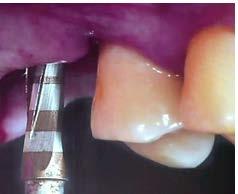

El protocolo de oseodensificación se ejecutó siguiendo una secuencia de fresado en sentido antihorario, salvo por la fresa piloto inicial, que operó en sentido horario a 1200 rpm, bajo abundante irrigación con solución fisiológica. Se inició el procedimiento con una fresa Versah de 2.5 mm de diámetro, hasta alcanzar una profundidad de 5 mm, seguida por una fresa de 3.0 mm hasta los 8 mm de profundidad. Posteriormente, se empleó una fresa de 3.2 mm hasta los 9 mm de profundidad para elevar la membrana sinusal en esta fase del protocolo.

Figura 3. Protocolo de fresado quirúrgico: a) fresa piloto sentido horario, b) comprobación radiográfica, c) RX pin de paralelismo, d) fresa 2.3 sentido antihorario, e) comprobación radiografía periapical de posición y elevación del piso de seno, f) fresa 3.2 a 9mm con elevación evidente, g) verificación de profundidad con sonda del kit de implantes, h) colocación de injerto de hueso NovaBone, i) vista del hueso en el lecho quirúrgico j) fresa final diámetro 4.3, k) RX de comprobación de fresa 4.3 y l) RX de implante e injerto colocados.

fresado (fresa de 4.2 mm de diámetro) dentro del sitio preparado como indica el protocolo de fresado Versah. Gracias al diseño específico de las fresas, el biomaterial fue distribuido hacia las zonas superior y lateral del sitio quirúrgico para promover una adecuada condensación ósea y facilitar la colocación del implante en una posición subcrestal de 1 mm.

Entre cada cambio de fresa, se verificó radiográficamente la dirección y profundidad del fresado. Finalmente, se completó el protocolo con el uso de la fresa de 4.2 mm de diámetro hasta alcanzar una profundidad final de 9 mm. Se obtuvieron imágenes radiográficas que evidencian la correcta colocación del injerto en la elevación lograda (ver Figura 3).